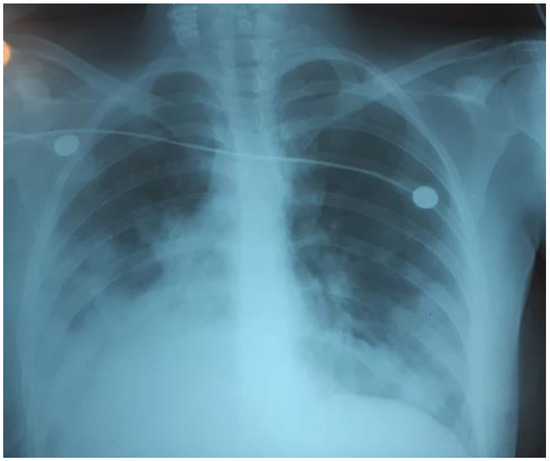

On the third day of mechanical ventilation, the girl had a complication—left-sided pneumothorax. The urgent drainage of the pleural cavity (Figure 4) was performed, as well as reduction of mechanical ventilation parameters: P/SIMV, FiO2 80%, PIP 12 cmH2O, PEEP 8 cmH2O, I/E 1-1.5, TV 300 mL/kg.

Figure 4.

Left-sided pneumothorax.

Over the next 24 hours, there was a progressive decrease in oxygenation: PaO2/FiO281, PaO2 80 mmHg, PaCO2 61 mmHg. The chest radiograph showed that the left lung was partly collapsed; there was an active air discharge through the drainage. The drainage of the left pleural cavity and the second drainage were performed (Figure 5).

Figure 5.

The left lung was partly collapsed.